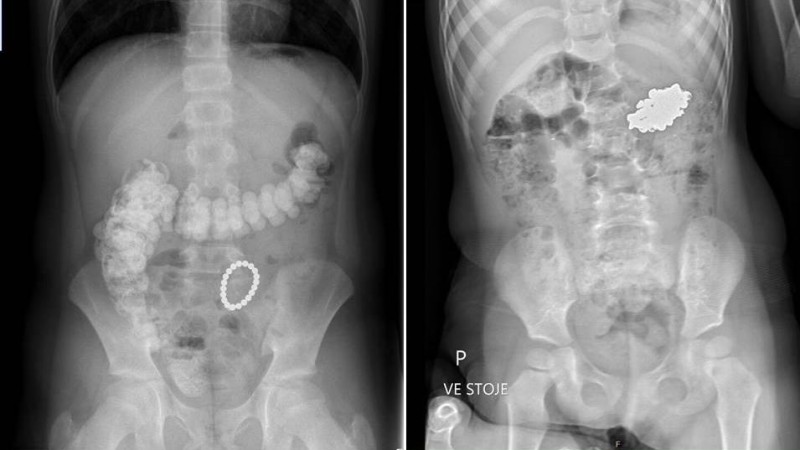

K dispozici jsou také skutečné RTG snímky, které jsou anonymizované a byly poskytnuty z Kliniky dětské chirurgie FN Brno, viz foto.